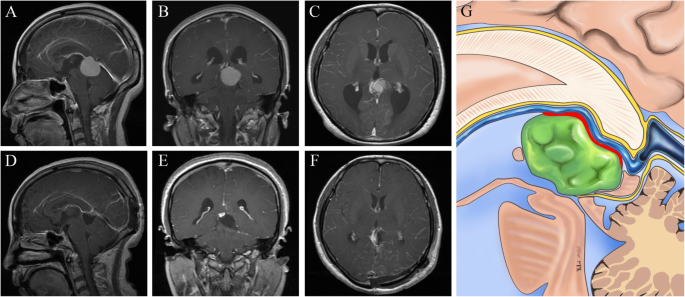

Radiological imaging of the tumor in the anterior superior part of the ICVs and the GV. a-c: Preoperative images showing a pineal region meningioma. d-f: Postoperative images showing gross-total removal of the tumor. g: Schematic representation of the microanatomical relationship between the tumor origin and arachnoid membranes. (Yellow lines represent the arachnoid membrane; Red line represent possible tumor attachment)

The origin of meningiomas in pineal region was studied by imaging examination combined with intraoperative verification among this group of patients. Of the 21 cases of tumor, 12 cases were confirmed to be FT meningiomas, which was directly related to the the dura of FT junction; 9 cases should be classified as VI meningiomas, which had no direct relationship with the dura of FT junction according to the current commonly used classification of pineal meningiomas. However, only one case of the 9 patients originated from the posterior segment of the ICVs within the VI (Fig. 4), the other case from the posterior part of the pineal gland, and the other 7 cases from the arachnoid sleeve of the GV.